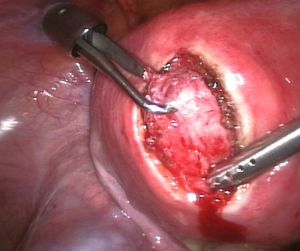

근종 절제술은 하나 이상의 자궁근종을 제거하는 수술이다. 보존적 치료 옵션이 실패하고, 가임력을 보존하거나 자궁을 유지하려는 환자에게 보통 권장된다.[60]

근종 절제술에는 세 가지 유형이 있다.

- ''자궁경 수술'' 근종 절제술(''경자궁경부 절제술''): 절제경, 질과 자궁경부를 통해 삽입하여 조직을 절단하는 데 고주파 전기에너지를 사용할 수 있는 내시경 도구를 사용하거나 이와 유사한 장치를 사용하여 자궁근종을 제거.

- ''복강경'' 근종 절제술: 배꼽 근처의 작은 절개를 통해 수행. 의사는 복강경과 수술 도구를 사용하여 자궁근종을 제거. 복강경 근종 절제술이 개복 근종 절제술보다 낮은 이환율과 더 빠른 회복을 보인다.[61]

증상이 있는 경우에는 치료가 필요하다.[79] 치료법으로는, 임신을 희망하는 경우 GnRH유사체 투여로 근종을 축소시킨 후 근종 절제술을 시행하고, 임신을 희망하지 않거나 악성 소견이 보이는 경우에는 단순 자궁 절제술을 시행한다.[82] 근종 절제술에는 복식(개복), 질식, 복강경, 자궁경 하 방식이 있다. 자궁경 하 방식은 장경 3cm 정도의 점막하 근종에 적합하다. 수술 외의 치료법으로는 자궁 동맥 색전술[82]이나 고강도 집속 초음파 치료 등이 알려져 있다.